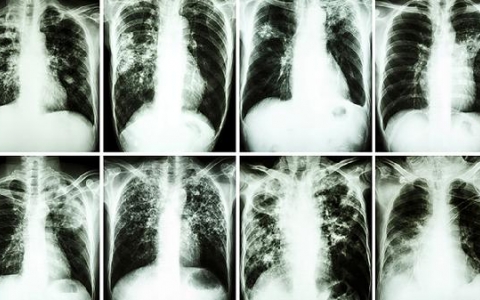

肺结节ct能看得出来吗

肺结节是否能通过CT检查看出来?答案是肯定的。CT扫描通常能够有效地检测到肺结节的存在。如果怀疑自己有肺结节,建议尽快去医院的呼吸内科就诊,医生可能会安排血常规